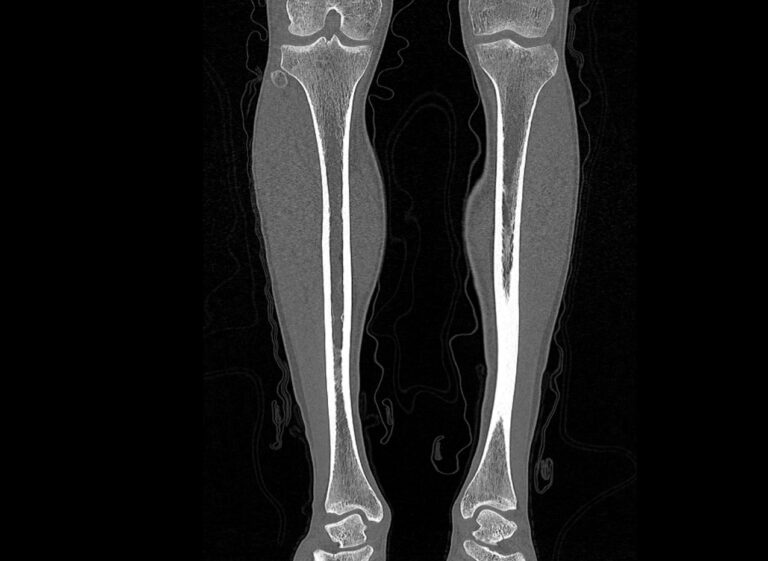

Наиболее информативным методом исследования костных структур и мягких тканей голени является мультиспиральная компьютерная томография. КТ относится к лучевым методам исследования и основана на применении ионизирующего излучения и последующей цифровой обработке данных, полученных при КТ-сканировании.

В наших медицинских центрах обследование области голени проводится на современных мультиспиральных компьютерных томографах последнего поколения TOSHIBA AQUILION. При помощи рентгеновских лучей аппараты послойно сканируют исследуемую область с толщиной среза от 0,5 мм. В результате получаются детальные снимки и цифровые трехмерные изображения в мельчайших подробностях. При этом пациент получает уменьшенную дозу рентгеновского облучения.

Мультиспиральная компьютерная томография позволяет оценить структуру костей голени, выявить переломы, воспалительные изменения, участки деструкции костной ткани, диагностировать опухолевые образования.